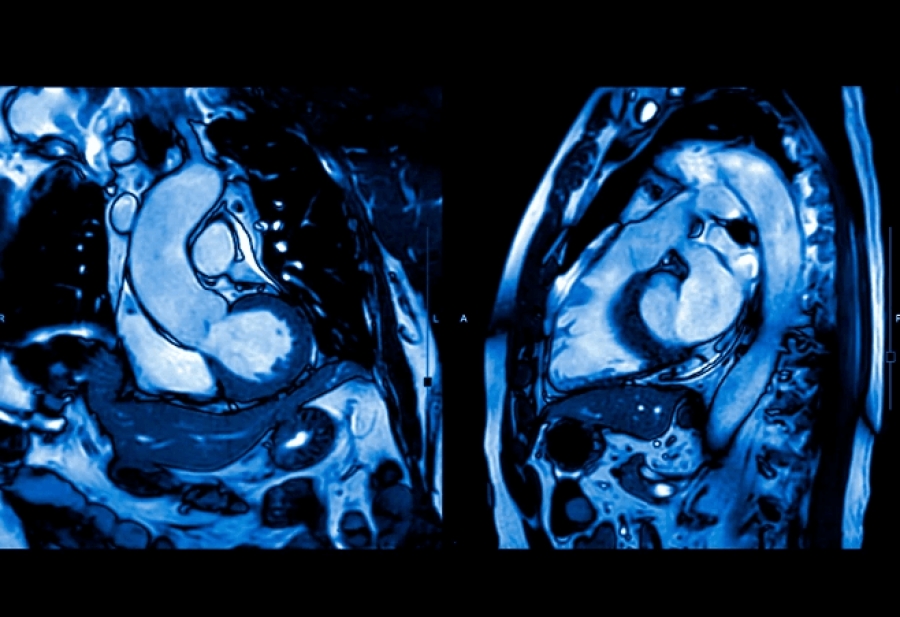

Γράφτηκε από Ένωση ΠαιδιάτρωνΜια νέα μελέτη δείχνει ότι η μαγνητική τομογραφία καρδιάς υπό κόπωση (stress MRI) μπορεί να αποκαλύψει μορφές στηθάγχης που δεν εντοπίζονται με την κλασική αγγειογραφία, ειδικά στις γυναίκες. Ένα βήμα προς την πιο ακριβή και εξατομικευμένη διάγνωση καρδιακών παθήσεων.

Σε αυτές τις περιπτώσεις, ο γιατρός προτείνει τη χρήση καρδιακής μαγνητικής τομογραφίας υπό κόπωση (stress cardiac MRI), η οποία επιτρέπει την παρακολούθηση της ροής του αίματος στην καρδιά ενώ ο ασθενής βρίσκεται σε κατάσταση «άσκησης». Αυτή η μέθοδος, σύμφωνα με τον Berry, είναι ιδιαίτερα χρήσιμη στις γυναίκες, που συχνότερα παρουσιάζουν στηθάγχη μικρών αγγείων, η οποία συχνά περνά απαρατήρητη.

Η ερευνητική ομάδα μελέτησε 250 ενήλικες με πόνο στο στήθος αλλά χωρίς φραγμένες αρτηρίες σύμφωνα με την αγγειογραφία. Όλοι υποβλήθηκαν σε εξέταση stress MRI καρδιάς, με στόχο να εντοπιστούν πιθανά προβλήματα στη ροή αίματος των μικρότερων αγγείων.

Τα αποτελέσματα ήταν εντυπωσιακά: όταν οι γιατροί είχαν στη διάθεσή τους τις εικόνες της μαγνητικής τομογραφίας, περίπου οι μισοί ασθενείς διαγνώστηκαν με μικροαγγειακή στηθάγχη. Αντίθετα, όταν η διάγνωση βασιζόταν μόνο στην αγγειογραφία, το ποσοστό αυτό ήταν λιγότερο από 1%.